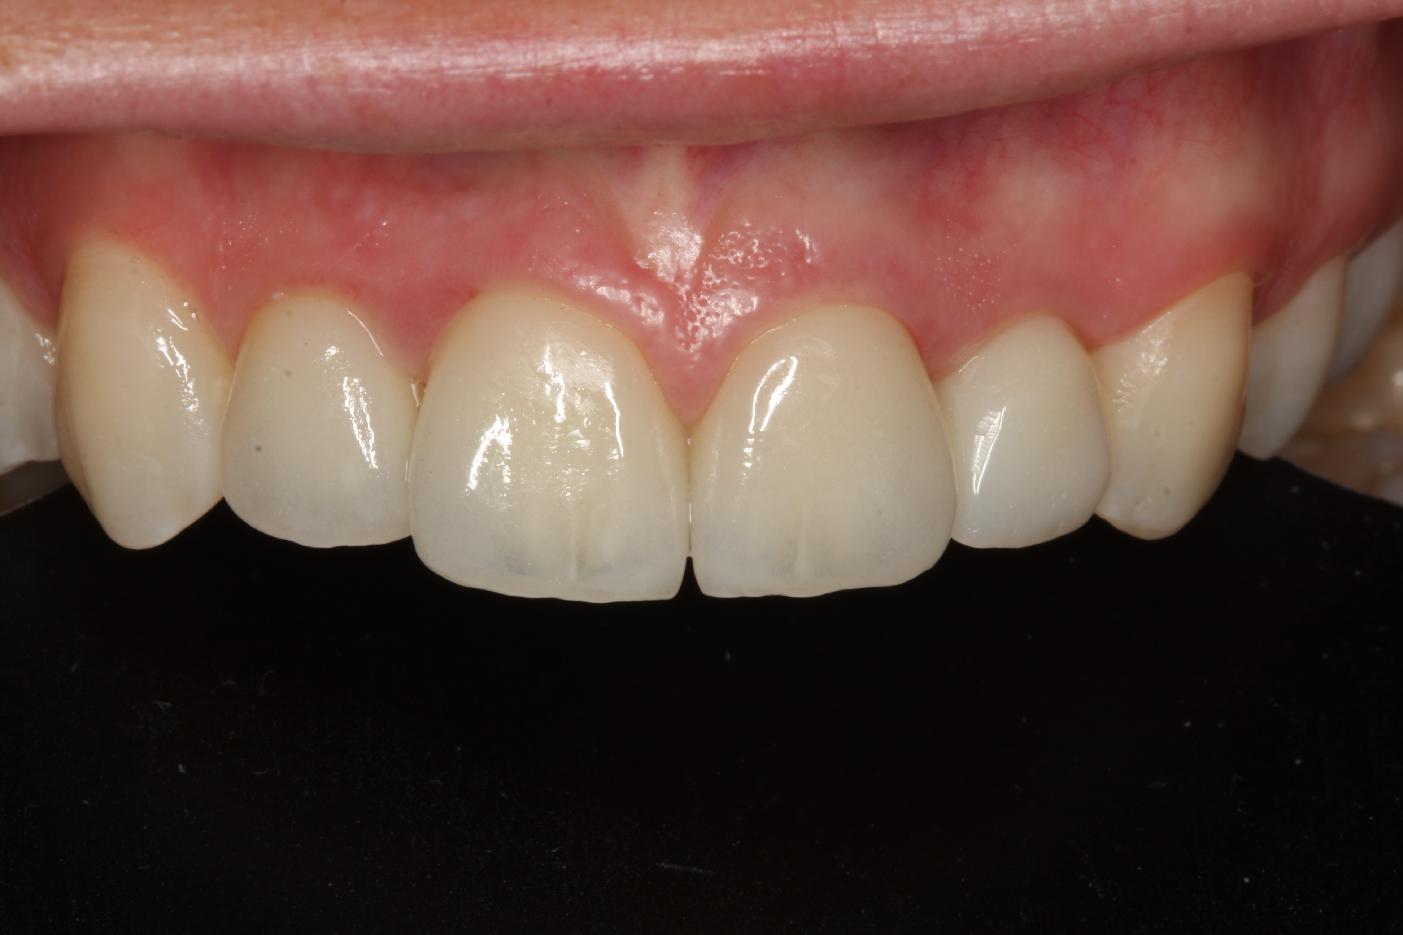

12/12 - Final outcome 18 months post-operativeSoft tissue thickening at immediate implant placement and GBR with mucoderm® and maxgraft® - Dr. A. Puisys